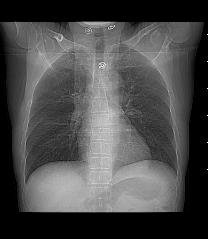

以下是引用liaoqiang在2008-3-21 17:45:00的发言:[br]右上叶尖段、后段有多发小结节和小条状影。考虑感染(结核可能性大。)。建议治疗后复查。

以下是引用王2008在2008-3-21 17:38:00的发言:[br]右上叶后段沿纹理走向呈串珠状.边缘欠清密度增高影,局部胸膜增厚.[br]考虑1.右上支扩可能.2.右上炎症.建议治疗后复查.请各位老师指教.

以下是引用lj11119999在2008-3-21 18:15:00的发言:[br]右上叶尖段、后段有多发小结节和小条状影。考虑感染(结核可能)建议进一步检查!